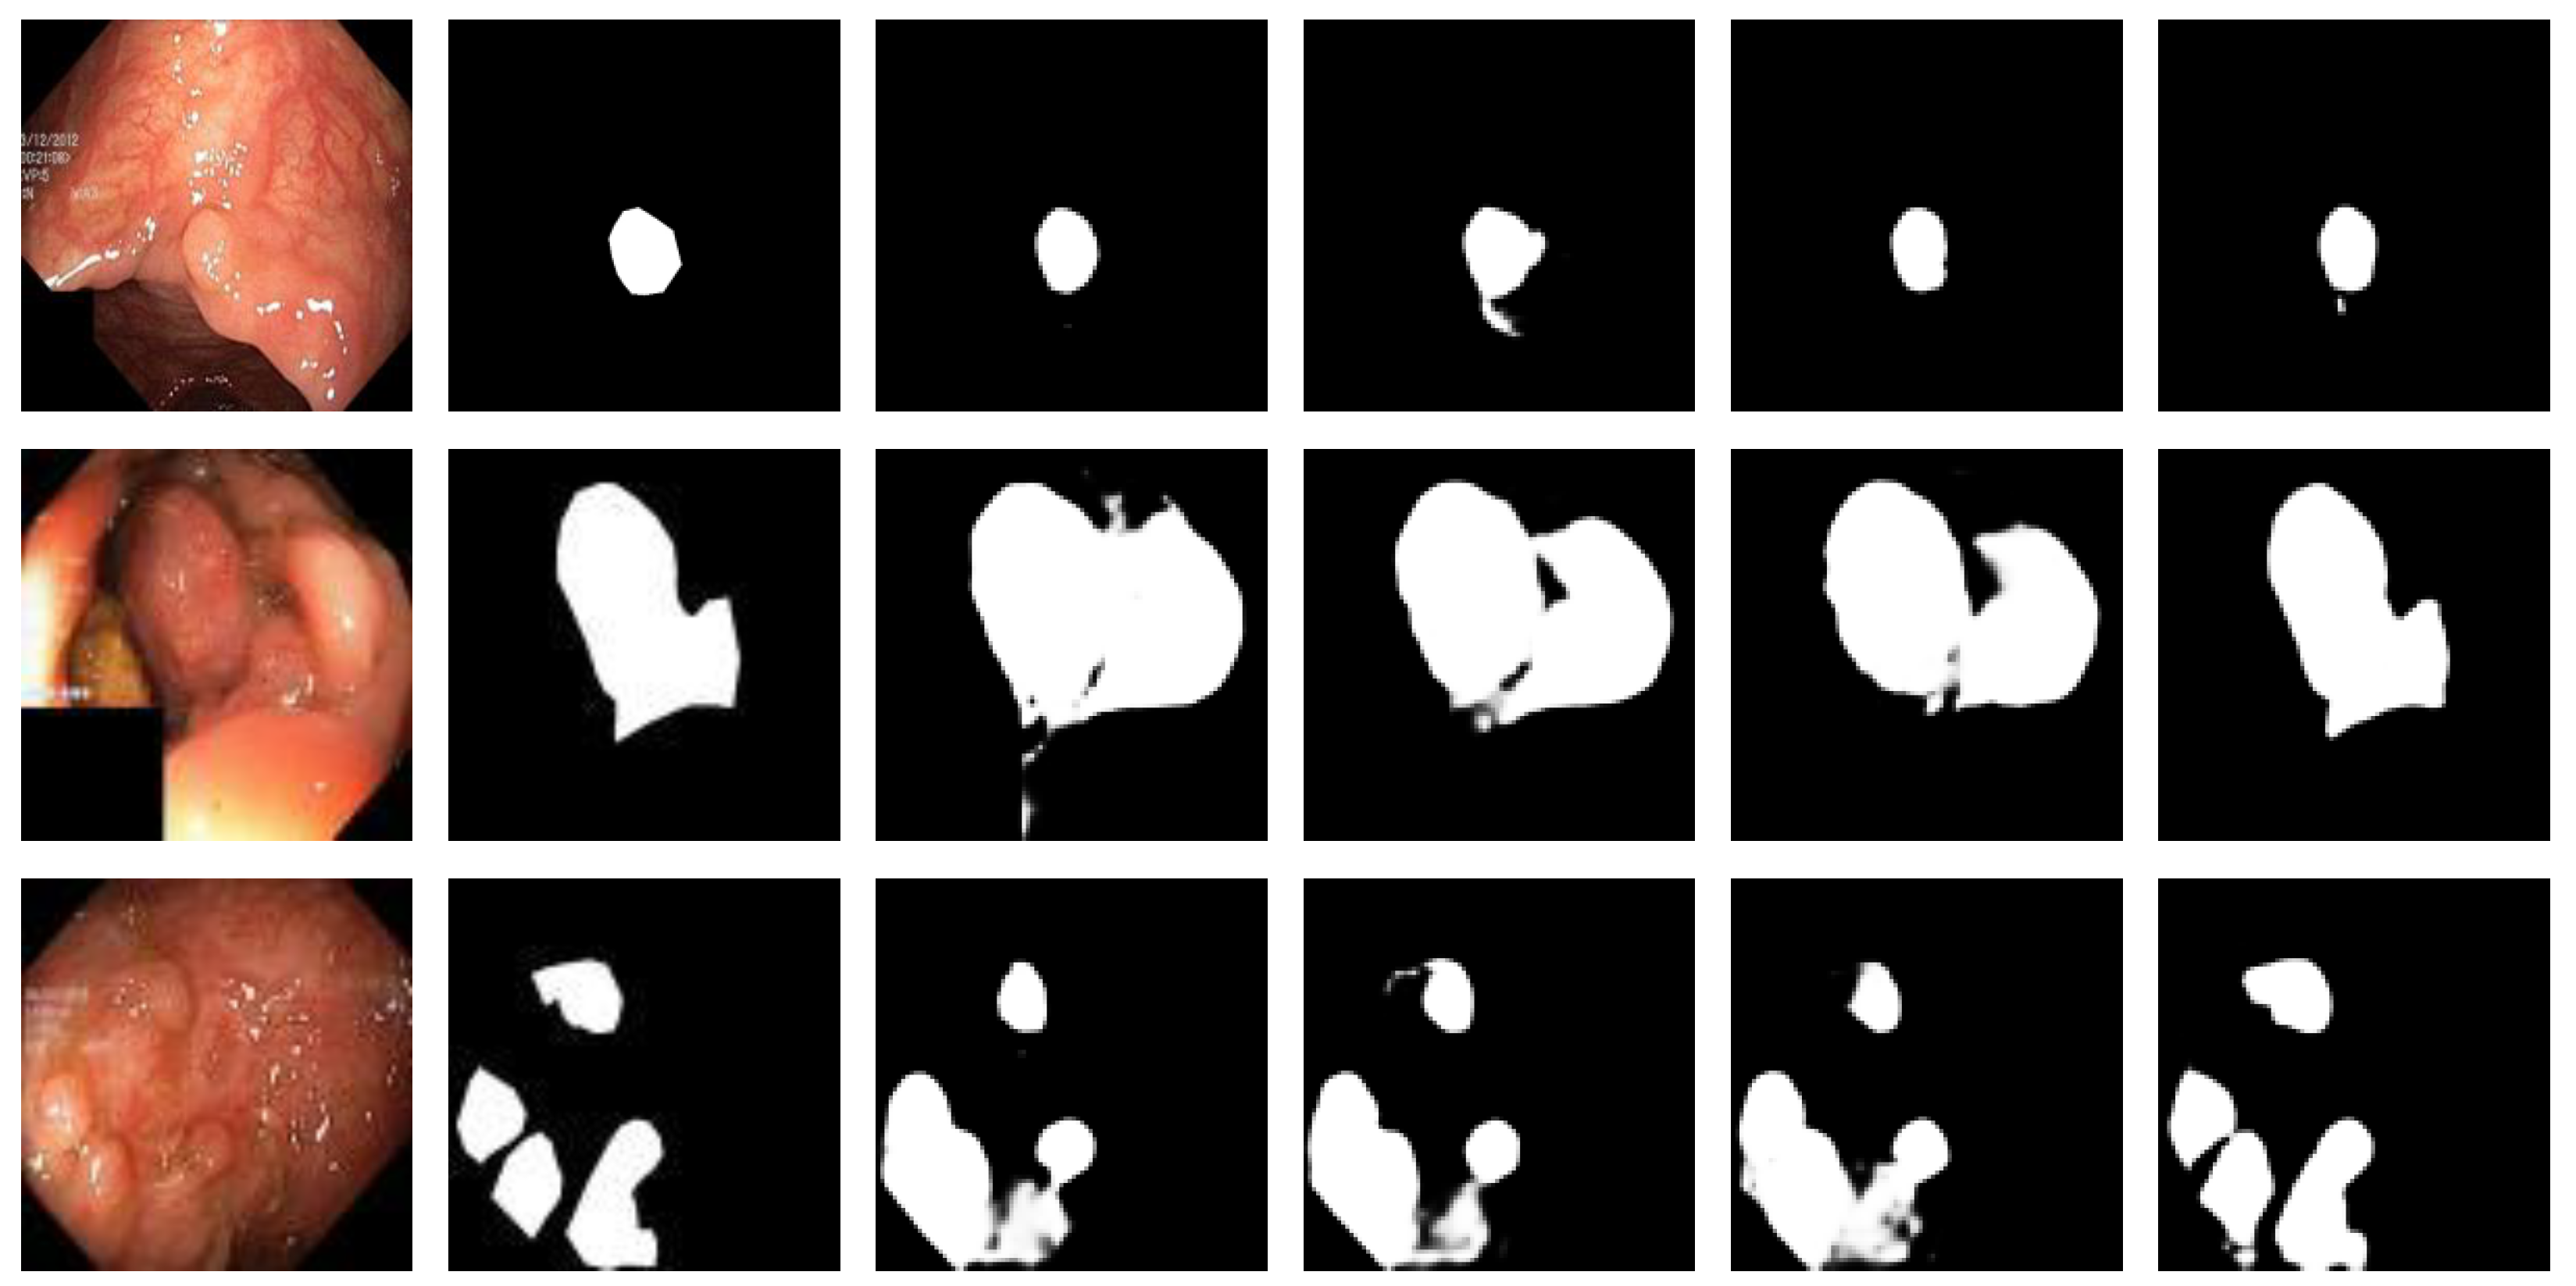

3.5. Experimental Results